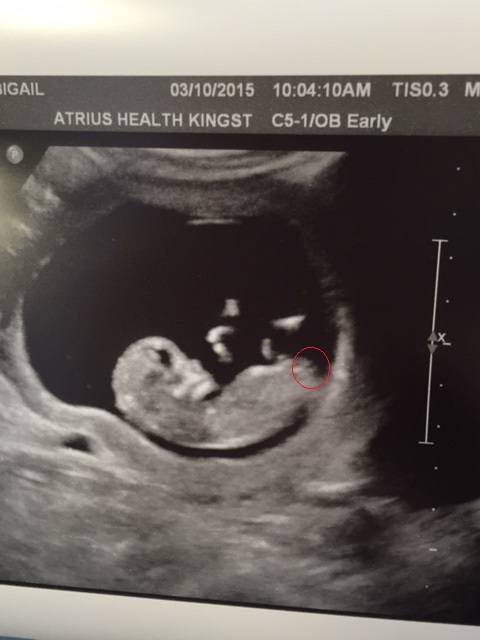

You were right about my little girl last time when I posted here 2 years ago! I know it's early but I'd love any initial guesses for baby #2. I am just under 12 weeks. Thank you in advance!

I'm not sure I see a nub here.

Too early for me to guess plus I don't think that's a nub! X

Skull theory girl

too soon to guess, genitals are not formed yet